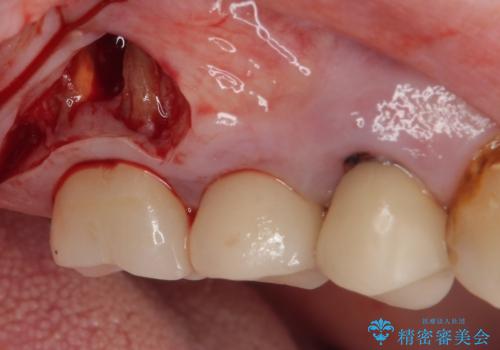

最新の症例

Latest cases